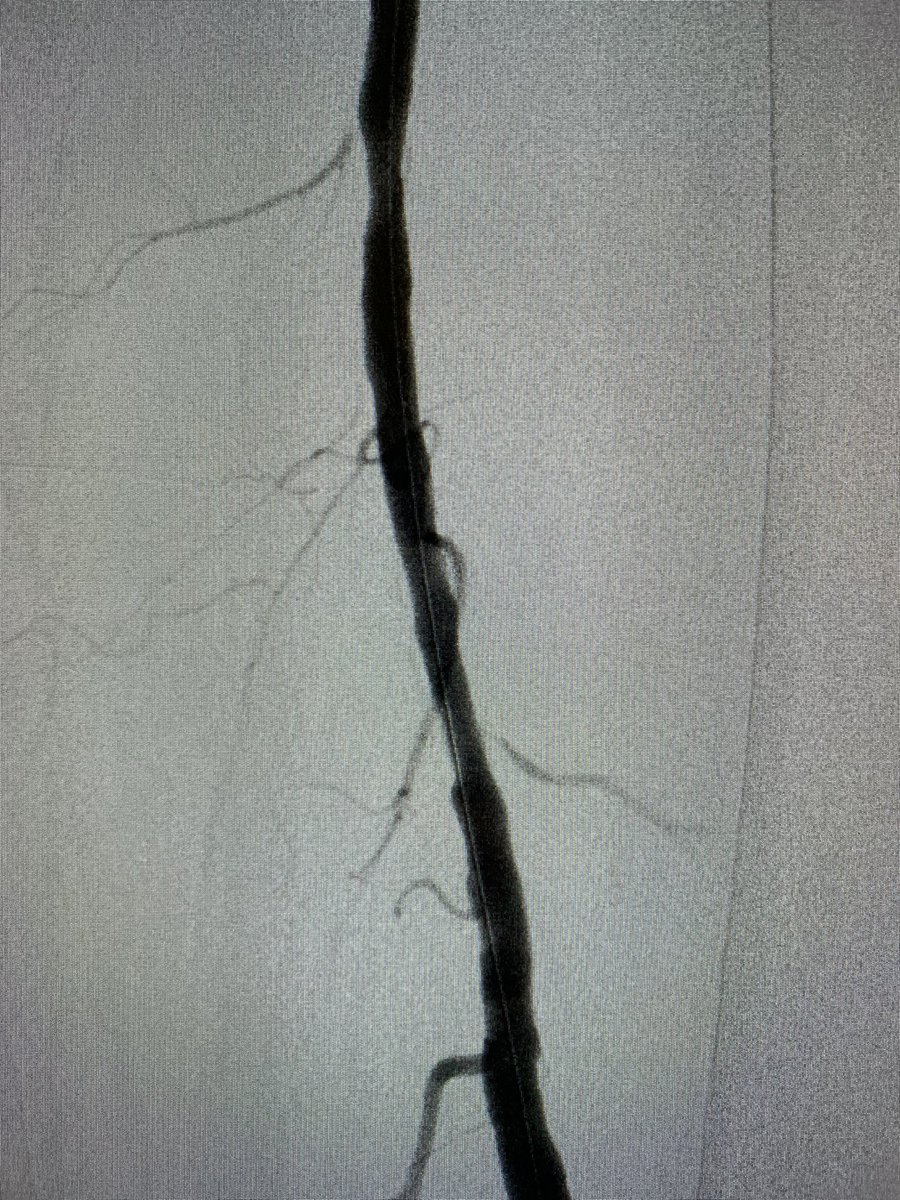

Patient with multiple small arterial ulcers involving the toes 1-3 with poor runoffs. Targeted recanalization of the AT with great flow to the wound. This patient will be plugged into our clinic and watched closely to assess healing.